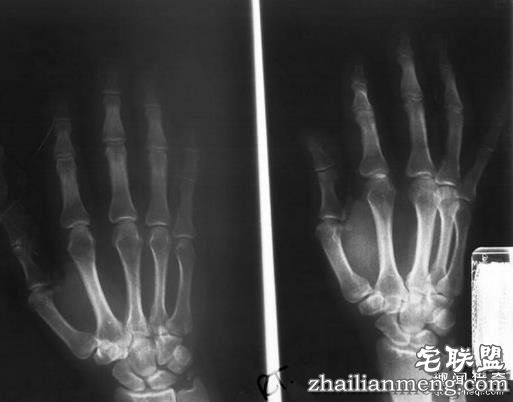

1895 年的一天,德国物理学家威廉 · 伦琴在德国维尔茨堡大学的实验室中忙碌地研究阴极射线管的特性时,突然注意到一束光投射到了屋内另一头的 ” 氰亚铂酸钡 ” 荧光纸板屏幕上,接着他发现纸板屏幕上出现了一只形同骷髅的手掌骨骼,他最初的惊讶顿时变成了震惊。

伦琴很快意识到,一些神秘的辐射光不但穿过了空气、并且穿过了他的血肉,从而使他的手掌骨骼投影在了光线暗淡的纸板屏幕上。这种光的粒子显然能够穿过固态物体,伦琴接着发现,他可以借助这种超乎想像的辐射光来产生清晰的体内图像。就这样,世界上第一幅 X 光片诞生了。X 光之所以叫 X,是因为 X 是未知事物的代称。没多久,世界各地的科学实验室都开始复制出 X 光机,20 年后,X 光开始大量用于医学目的。由于 X 光是大自然的一种现象,所以准确地说,伦琴是意外发现了 X 光,而不是发明了 X 光。